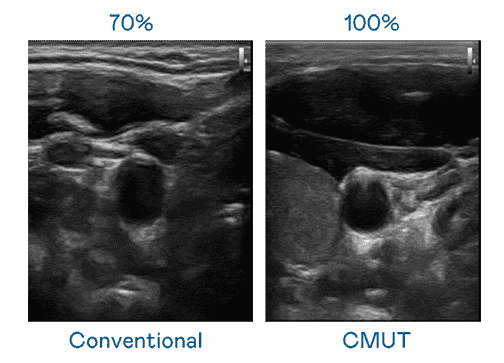

CMUT 技术是一种用电容式微机电元件来产生超音波讯号的技术。。与传统 PZT 压电式技术相比,,,CMUT 频宽增加 30%,,,更宽频的超音波讯号让影像解析度大幅提升,,,,是实现高影像品质医疗超音波扫描、、促进精准医疗发展的关键技术。。。

大频宽带来超清晰影像

超音波影像的解析度高低,,首先取决于探头能发出的讯号频宽。。。EBpay CMUT 可提供高清晰的超音波讯号,,,,提供高频宽、、、、高灵敏度、、、、影像纹理细节更高的超音波影像,,,,协助医护人员缩短影像判读时间及利用精准的医疗影像进行诊断。。。。